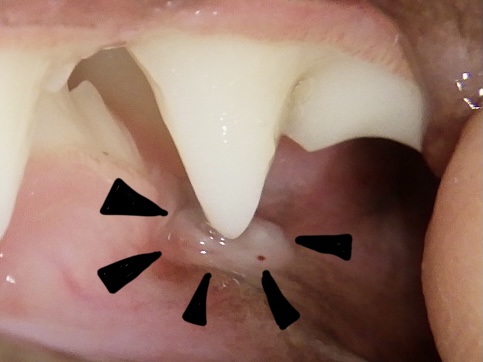

乳歯が抜けたあと乳歯が2本ぬけた写真です。 乳歯は、大人の歯に根っこを食べられて、ぐらぐらになっていきます。 写真の下の歯が先にぬけて何日もたっています。抜けた数日は柔らかい歯茎 肉芽 になっています。 その肉芽が自然に吸収されたり取れたりして、大人の。

乳歯が抜けた後、肉芽に乳歯のかけら - 赤ちゃん・こどもの症状 - 日本最大級 医師に相談できるQ&Aサイト アスクドクターズ。

乳歯抜けた後に小さい歯肉?ぶら下がってる!大丈夫?何か調べてみた│SUKKIRI。

乳歯が抜けたあと乳歯が2本ぬけた写真です。 乳歯は、大人の歯に根っこを食べられて、ぐらぐらになっていきます。 写真の下の歯が先にぬけて何日もたっています。抜けた数日は柔らかい歯茎 肉芽 になっています。 その肉芽が自然に吸収されたり取れたりして、大人の。

乳歯が抜けた後に肉芽!?理由とその後の経過を記録しました! 体験談・画像ありナース“みかん”のブログ。

ファーストキッズTVのめーちゃん on X: "昨日かなたの乳歯が抜けました🥹👏 でも何か残ってる😳‼️ これって大丈夫ですか?わかる方教えてください🥺✋乳歯が抜けた5歳児はじめて記念日 https:t.co aWGHu8FfQw"X。